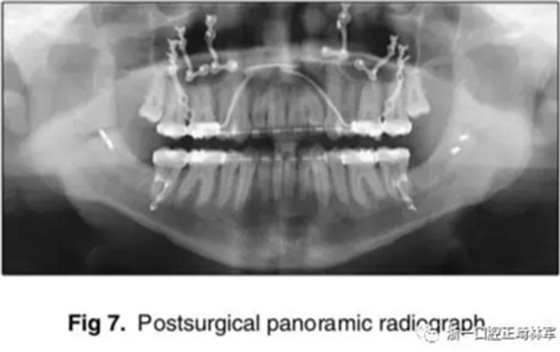

手術(shù)先采取下頜骨雙側(cè)矢狀劈開(kāi)截骨術(shù),使用中間合板確定下頜位置。當(dāng)下頜骨位置穩(wěn)定后,使用堅(jiān)固內(nèi)固定固定下頜骨,移去中間合板。隨后,上頜行LeFort I型截骨術(shù),按照Dolphin軟件的計(jì)算前移7mm;通過(guò)終末合板確定上頜骨的位置,再使用鈦釘進(jìn)行堅(jiān)固內(nèi)固定。拔除第三磨牙;同時(shí),在顴突處植入微鈦板,使用骨皮質(zhì)螺釘固定。

術(shù)后,患者即刻獲得了I類(lèi)側(cè)貌,II類(lèi)尖牙關(guān)系。